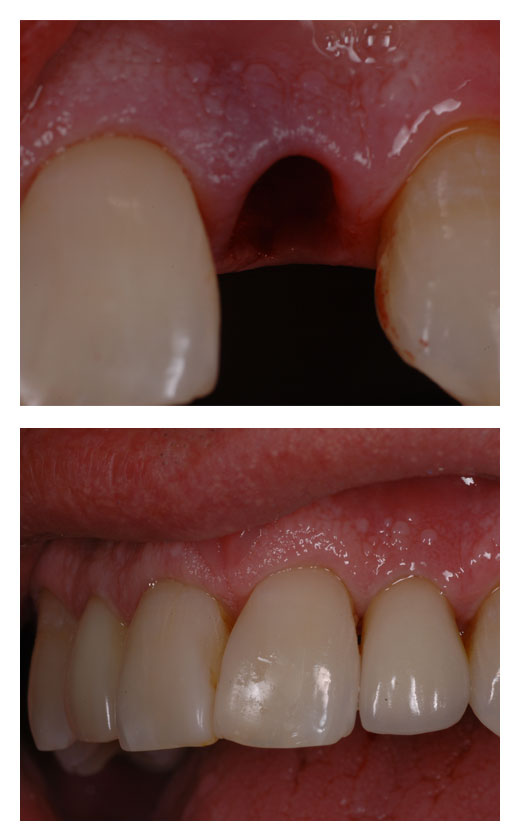

Questa branca si occupa di sostituire le radici perse con strutture in titanio che supportano elementi protesici. Grazie agli impianti è possibile sostituire denti singoli, intere arcate, selle edentule, stabilizzare dentiere.

Con l’apporto della chirurgia computer guidata in carico immediato la riabilitazione si realizza in poche ore e con un minimo disconfort post operatorio.